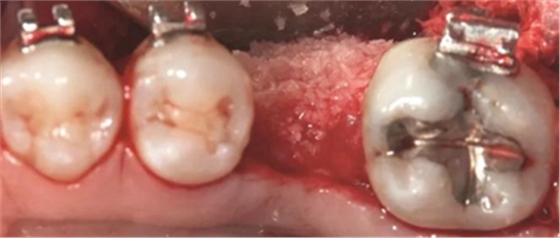

圖5g. 3 個(gè)月后完成了位點(diǎn)加速改建,近遠(yuǎn)中向的修復(fù)空間和頰舌向的骨增量均增加

術(shù)后3個(gè)月,右側(cè)第一磨牙的空間約為9mm(3個(gè)月中增加了1.6mm),逐漸接近了對(duì)側(cè)第一磨牙的空間(也約9mm)(圖6a)。術(shù)后7個(gè)月的錐束CT顯示,右側(cè)第一磨牙區(qū)域獲得了2.5mm的水平骨增量(圖6b 和c)。左側(cè)第一磨牙的無(wú)牙區(qū)保持相同的尺寸,在種植體植入前也需要骨增量。